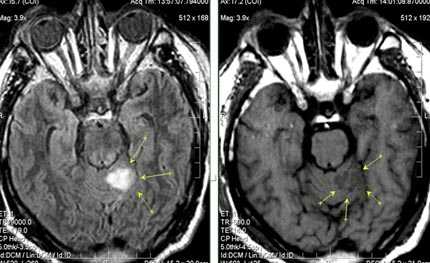

Внутримозговая гематома (граница острой и ранней подострой стадий - 3 суток), осложнившаяся внутрижелудочковым кровоизлиянием.

Внутримозговая гематома, поздний подострый период (14-21 день) с перифокальным отеком вокруг гематомы.

Внутримозговая гематома правой теменной доли. Граница поздней подострой и ранней хронической стадии. В Т2-ВИ виден ободок гемосидерина (стрелка).

Хочется подчеркнуть возможность МРТ в выявлении последствий геморрагического поражения - остается хорошо дифференцируемый по Т2 ободок гемосидерина, недоступный для визуализации при других методах нейровизуализации.

Стрелками показан ободок гемосидерина по периферии постишемической кисты.